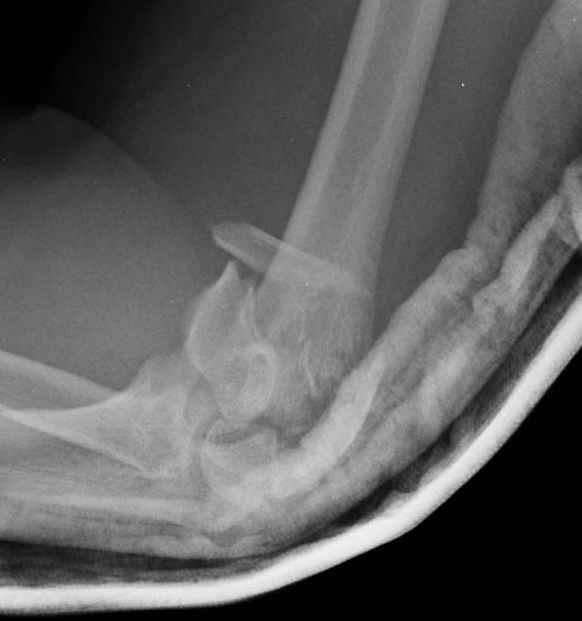

Уважаемые коллеги! Мужчина, 28 лет. 1 сутки назад получил бытовую травму - закрытый чрезмыщелковый перелом правой плечевой кости со смещением. По месту жительства в ЦРБ - репозиция, иммобилизация. Направлен к нам.

Место болезни без особенностей, неврологических и сосудистых расстройств нет. Принято решение об оперативном лечении - чрескостный остеосинтез.Предложения по конструкции АВФ (т.к. мнения расходятся)? Заранее благодарю! С уважением,А.В.ВладзимирскийДонецкий НИИ травматологии и ортопедииДонецк, Украина

Примерный случай, только перелом был открытый, в задне-медиальной стороне рана около 2 см по характеру "изнутри кнаружи", неврологический статус со слабостью сгибания мизинца, также слабая абдукция и аддукция указательного пальца и сгибания в кисти.

Больному сделали обработку и наложили временный аппарат внешной фиксации плечо-предплечье.

На шестой день сделали открытую репозицию чрезлоктевым доступом двумя locking plate, локтевой нерв был ушибленным, после операции положительная динамика в Flexor Carpi Ulnaris. Фиксацию локтевого отростка произвели tension band technique с дополнительным шурупом.

Этапы операции на снимках....